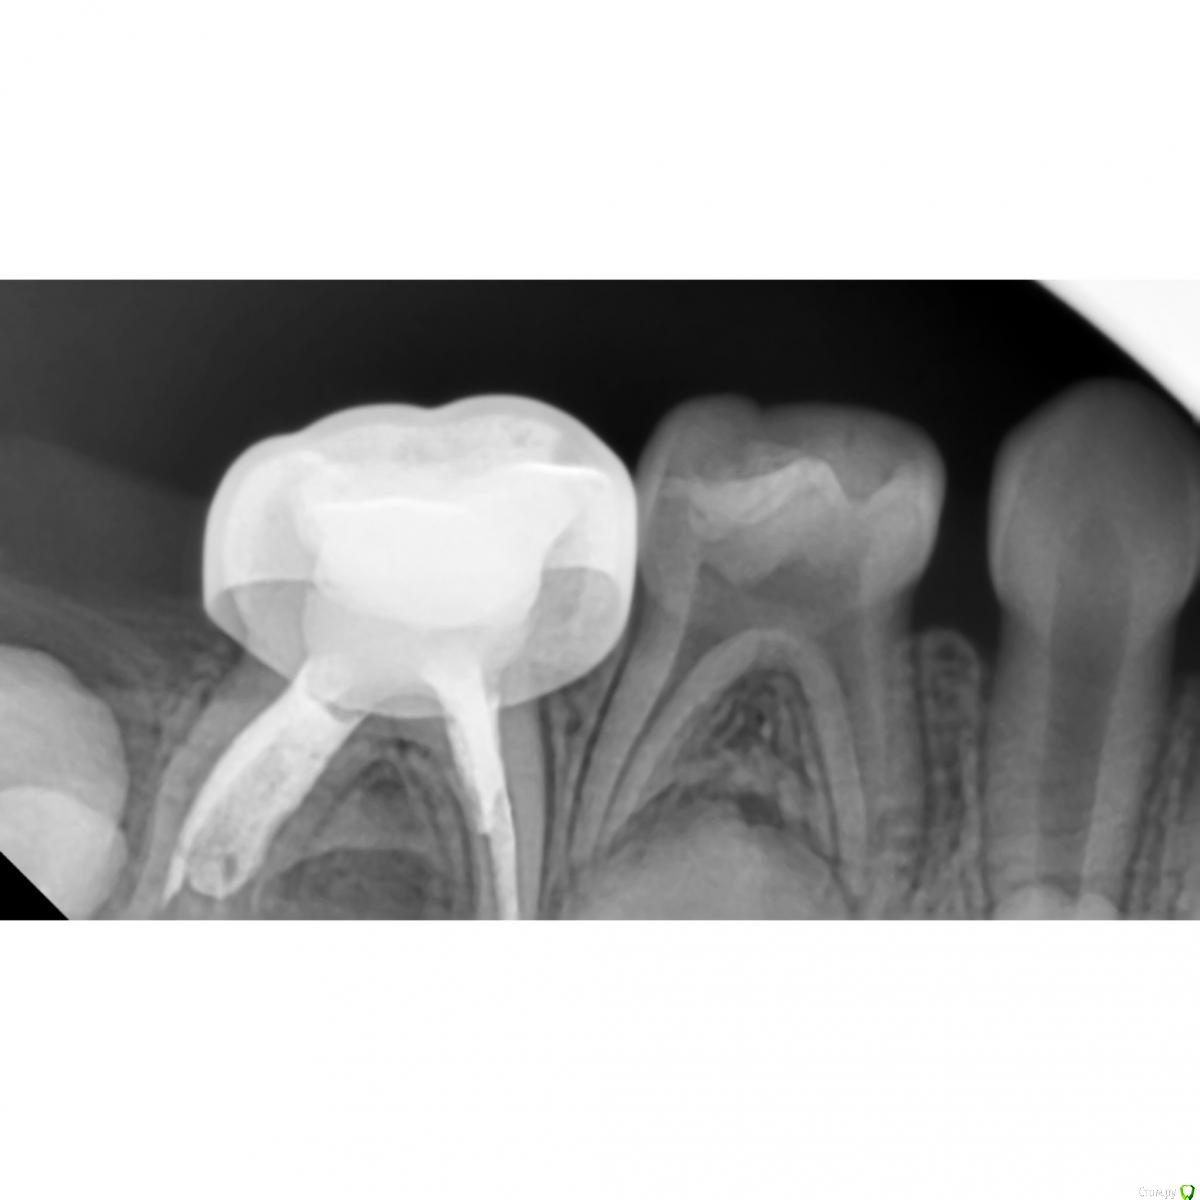

CRAZYDUCK Опубликовано 7 мая, 2018 Автор Поделиться Опубликовано 7 мая, 2018 (изменено) Лечение пульпита ; 6.4 необратимый , 6.5 обратимый .Продолжительность 1:15 час ( с момента входа в кабинет и до прощания )6.4-каналы -протейпер дентсплай Sx, ручные инструменты 25.02, гипохлорит 3,2%, пломбирование каналов Йодотин( отличный аналог метапекса , который всегда идёт из канюли в отличии от метапекса ), восстановление культи СИЦ, коронка 3М ESPE стальная .6.5 - ампутация , ХГ2%, спонтанный гемостаз , рутдент быстротвердеющий ( МТА), изоляция Calcimol, реставрация Charisma. Все лечение в одно посещение - долго для ребёнка 4 лет , но так лучше . Пришла к такому методу работы относительно недавно .Больше нравится работать таким образом - 2-3 рядом стоящих зуба в одно посещение . В этот раз было уже не до фото . Для начинающих коллег на rvg выделила полости кариозные и пульпарные полости. Изменено 7 мая, 2018 пользователем CRAZYDUCK 4 Ссылка на комментарий